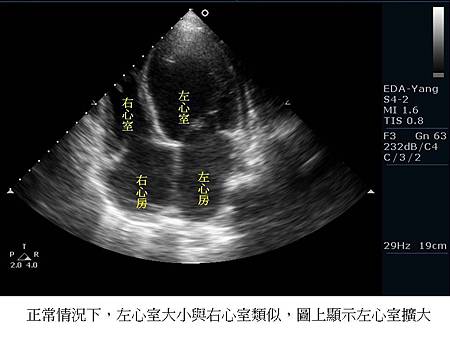

1. 左心室擴大的程度與上次相比結果如何?

左心室愈大,表示心臟擴大了,心衰竭的情況在惡化。「心室中膈缺損」造成心臟一點點擴大是必然的現象,是可以接受的。但是當心臟擴大到一定程度、胸部X光肺部充血嚴重、加上容易會呼吸急促,表示心臟衰竭變嚴重了,需要用藥,或考慮心導管、開心手術治療。關於心導管治療,可以看看想接受經心導管關閉心室中膈缺損(VSD)前,您必須知道的事!、如何用心導管技術關閉心室中膈缺損 (VSD)?